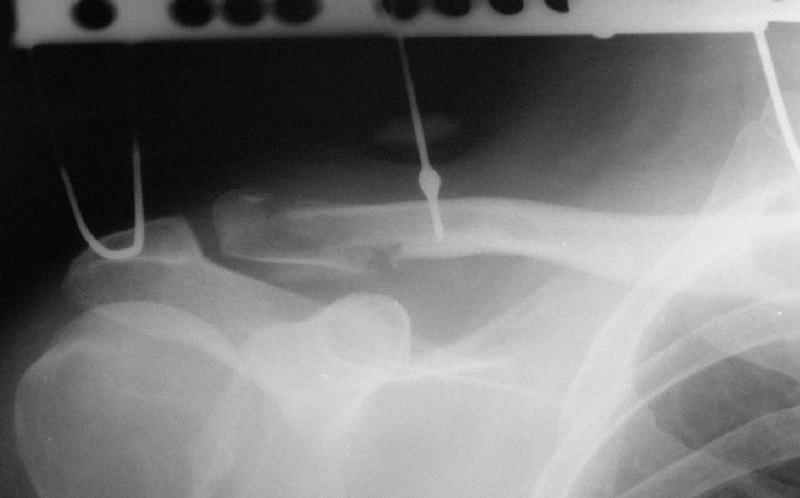

Действительно, на представленном вами первично снимке есть кусок спицы... Но что должно было произойти с больным (или что-то иное?), чтобы спица-толкатель сломалась ниже расположенного на ней упора? Оправдано ли использование таких спиц? Или аппарата?

Больной хоть и молодой но отнюдь не ребенок (судя по снимкам)... Почему было не использовать стержень-толкатель, если уж принято было решение за первичный ЧКОС?

И откуда такая любовь к аппаратам при данном виде травмы?

Первично правильно сопоставленный перелом (небольшой разрез, спицы) привел бы к тому, что костный фрагмент, отрванный ключично-клювовидной связкой, лег аккурат под своим ложем и тесно к нему... то бишь в итоге сросся бы без проблем... (кстати на вашем снимке костный фрагмент "оскольчатого перелома" консолидирован... то есть даже достигнутая вами несостоятельная фиксация привела к приростанию авульзионно оторванного

фрагмента)

То, что было представлено на вашем снимке - ... - создается впечатление что никакой консолидации в области перелома (основного) достигнуто не было...

Причина? Аппарат? Может быть центральный отломок был смещен кпереди или кзади?